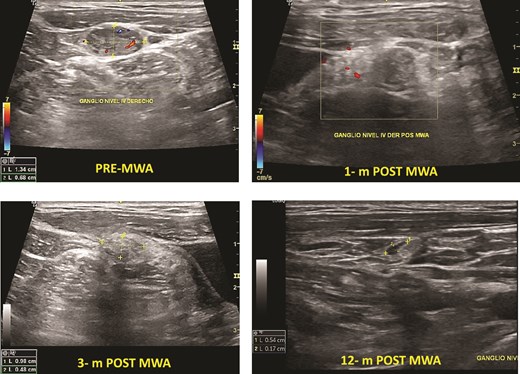

Cervical lymph node metastasis

Two patients had cervical metastasis of PTC confirmed by PAAF. Both were on the right side located on level 4. The longest diameter of the ablated LNs reduced from 13.0 (SD 4.0) mm to 5.0 (SD 3.1) mm (P < .001) at 6-month follow-up. Furthermore, the overall mean volume pre-MWA was 0.32 (0.2) ml. After ablation, the mean TN volume at 1-month, 3-month, 6-month, and 12-month were 0.22 (0.20) ml, 0.09 (0.10) ml, 0.45 (0.05), and 0.03 (0,01) respectively. The average s-Tg level pre-MWA was 10.5 (SD 7.0) ng/ml with anti-Tg <20, and it decreased to 1.23 (SD 1.1) ng/ml at 6-month and 1.12 ng/ml at 12-month follow-up (Fig. 3). There was no progression of CLN, distant metastasis, or high Tg during the follow-up.

Cervical lymph node PTC metastasis pre- and post-MWA (1, 3, and 12 months).